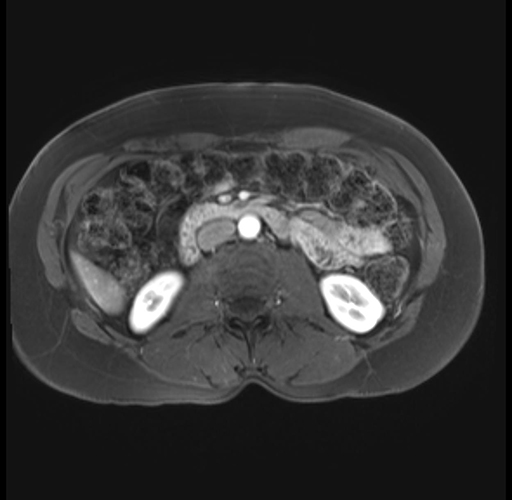

Imaging Analysis

Look through the patient's CT scan to identify any areas of concern for the necessary procedure.

Based on your CT findings, which issue(s) are present and would give reason for "planned slowing down moment(s)" in this case?

Considering a standard distal pancreatectomy procedure, what step(s) of the operation would you do differently in this case?